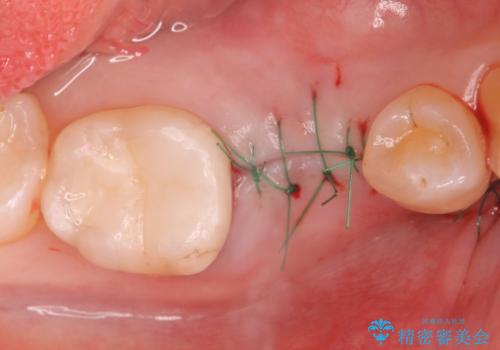

- 過去に抜けてしまった歯のところにインプラントを入れたいとの事で来院。

CTで確認したところ骨の高さや厚みがインプラント埋入できる状態でしたのでインプラント治療を行いました。